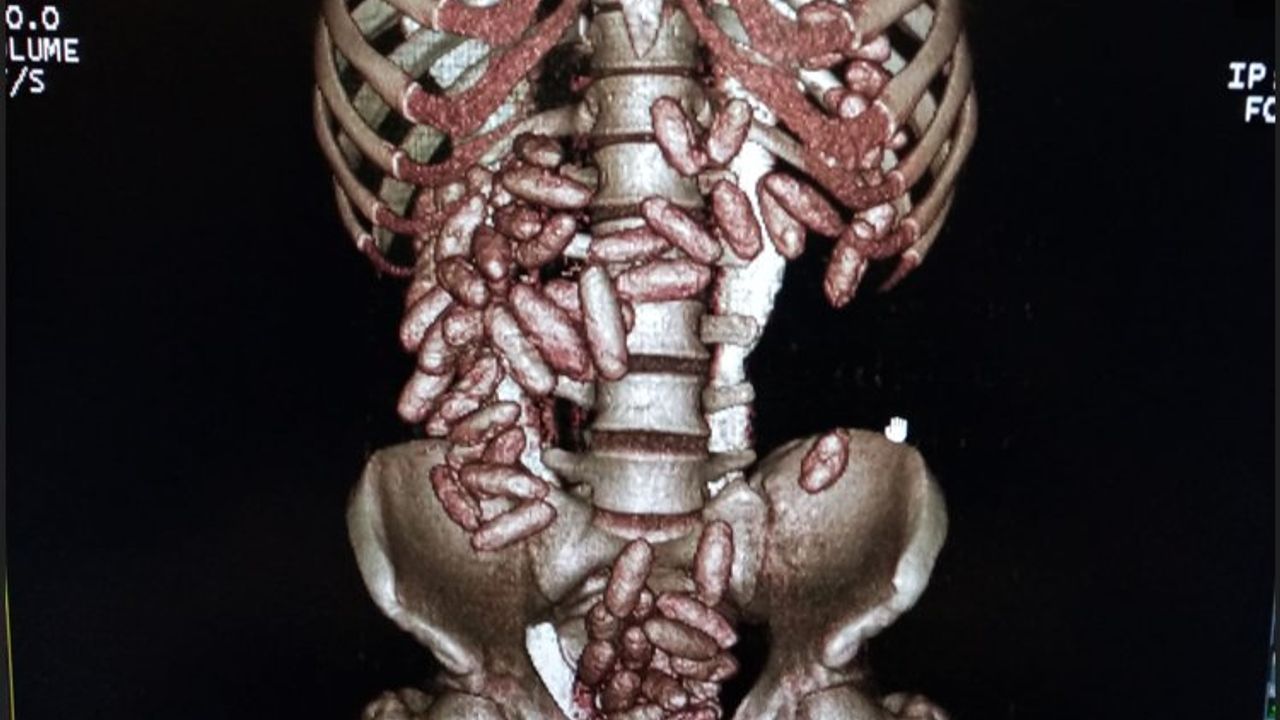

Alınan bilgiye göre uçağın iniş yapmasının ardından muhafaza ekiplerince yolcuyu fiziki takibe başladı. Gümrük kontrol noktasında durdurulan şahsın beraberindeki valizi X-ray taramasından geçirildi ancak valizde herhangi bir suç unsuruna rastlanılmadı. Fakat ekiplerin üst araması yaptığı esnada şahsın telaşlandığı görüldü ve akabinde şahsın karın bölgesinde şişkinlik olduğu fark edildi. Bunun üzerine tomografi cihazına alınan şahsın çok sayıda kapsül yuttuğu tespit edildi.

Sağlık kuruluşunda yapılan muayene ortaya çıkarılan kapsüllerin içerisindeki maddenin kokain olduğu belirlenirken, kuryenin 820 gram kokain yuttuğu belirlendi.